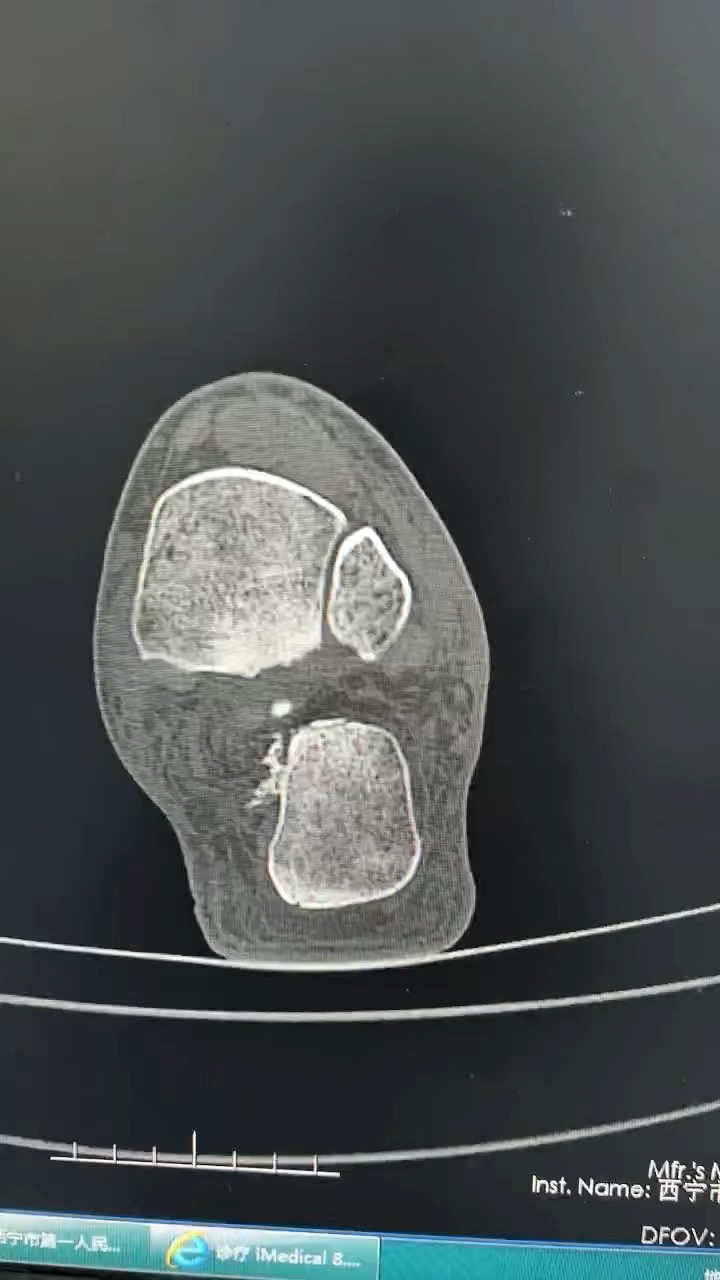

病例跟骨骨折(sanders IV)微创手术

【患者信息】:男性

【主诉】:外伤致左足疼痛10天

【现病史及既往史】:糖尿病

【检查】:外院跟骨骨折

【临床诊断】:跟骨骨折

【治疗经过及结果】:入院后行手术治疗